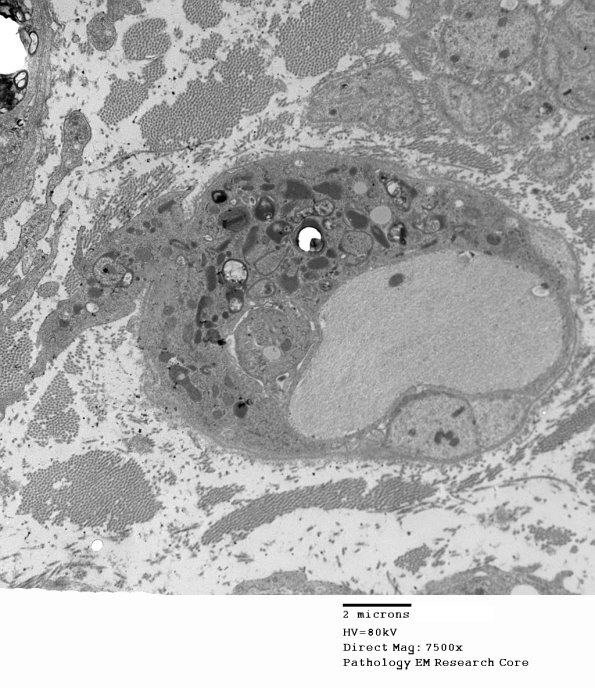

2F4A,B The axon is already demyelinated by the macrophage within the Schwann cell sheath which has two parts, one of which is in the endoneurial space. (electron micrograph)